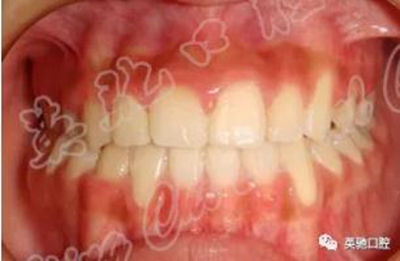

患者進行前牽引5個月。后期繼續(xù)排齊整平牙列,精細調(diào)整咬合關系。療程1年半。因為右上尖牙萌出不足,所以療程稍長,否則療程會明顯縮短。隨訪2年以上療效穩(wěn)定。